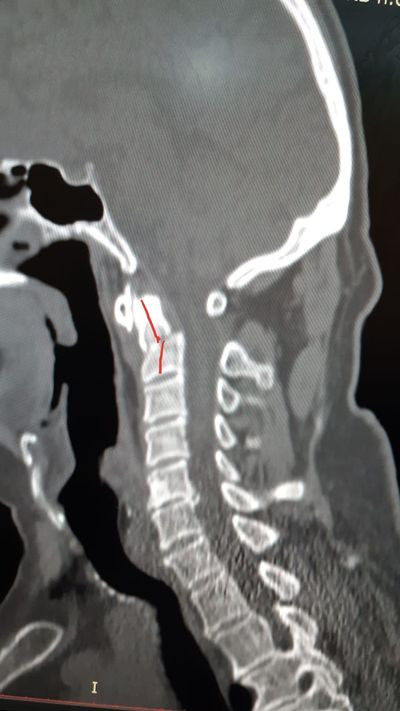

При обследовании было выявлено тяжёлое повреждение тела и зубовидного отростка второго шейного позвонка (он обеспечивает 80 процентов движения головы). Врачи отмечают, сложность данного случая в том, что эта область обильно кровоснабжается, и на момент поступления у пациента уже отмечалась грубая кифотическая деформация (ригидный наклон головы и невозможность её держать).

Для того, чтобы позвонок поставить на место пришлось использовать систему гало-фиксации. На туловище был установлен корсет, к черепу присоединено кольцо, через корсет на туловище обеспечивается тяга, за счёт которой постепенно выправляется смещённый позвонок и стабилизируется.